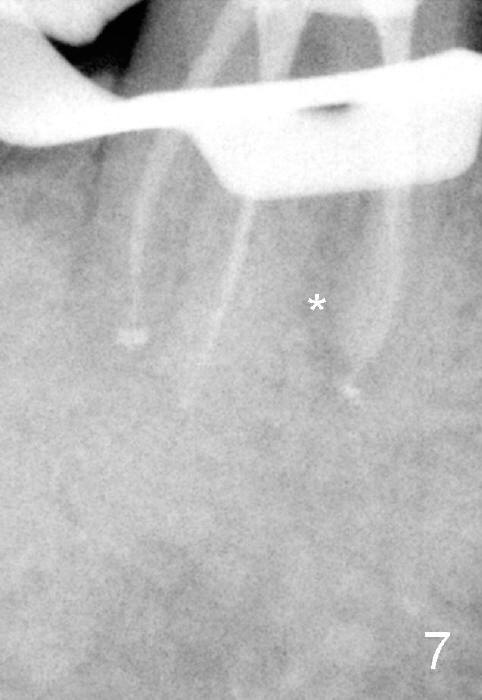

五十来岁郑先生缺失两个下颌第二磨牙,严重牙齿磨耗,三年前主诉右下第一磨牙冷热痛(可能与磨耗有关),近中有轻度根尖阴影(图一箭头),初步CT检查表明该牙齿有四个根管(图二,三),兴高采烈,这样不会错过远中舌侧根管(DL),开髓发现根管几乎阻塞,尤其是远中舌侧,hand files不容易进入根尖,使用20/.04 rotary file时,在根尖断裂(图四箭头,其余根管插入30/.06牙胶尖),一时不能bypass断针,暂封。十二天后,重新bypass断针,终于成功,但是取不出断针,扩大二十号hand file(远中舌侧根管),图五,图六侧方充填(lateral condensation)之前,图七之后(图六,七*:近中阴影)。根管治疗和牙冠之后一直无症状,一年半在第二磨牙处植牙(图八I),虽然第一磨牙近中根尖阴影增大(*),但离植牙还有一定距离,可能不会产生问题。不过不久植牙松动,病人自己取出,可能当时钻洞太大,而不够深(no primary stability),怕侵犯下颌神经(图八红线)。十个月后再次试图植牙(图九D:钻头),突然发现智齿(阻生)在手术视野之中,而且智齿咬合面不干净,结果取消植牙,把智齿拔除,这时病人第一磨牙仍没有症状,但是根尖阴影不可观(图九*),远中舌侧根尖好像没有病变(箭头)。大概这次智齿拔除也与左下智齿七拔除(左下第二磨牙植牙之前)一样不舒服,郑先生一直没有回来做右下第二磨牙植牙。上周六他终于登门,右下第一磨牙出现根尖脓肿症状(术后近三年),根尖片如图十。S代表已经愈合智齿牙槽窝,根尖阴影不小,断针根尖仍没有阴影。